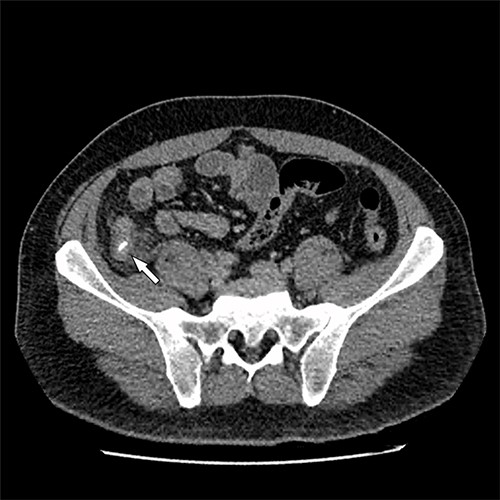

The patient had an uneventful recovery post operation. A retrospective review of the patient’s previous imaging revealed evidence of an appendicolith at the time of appendicitis diagnosis (Fig. 4). Despite the presence of the appendicolith on the preoperative CT, the histology of the resected appendix did not describe the presence of the imaged appendicolith. In addition, there was no evidence of a urachal lesion then on the initial imaging (Fig. 5), nor was there an intraoperative report of abdominal abnormalities during the appendicectomy. Therefore, it is hypothesized that the urachal lesion was an abscess secondary to the retained appendicolith from the appendicectomy.

Axial CT image. Arrow indicates appendicolith present within the appendix, with minor fat stranding surrounding the appendix.